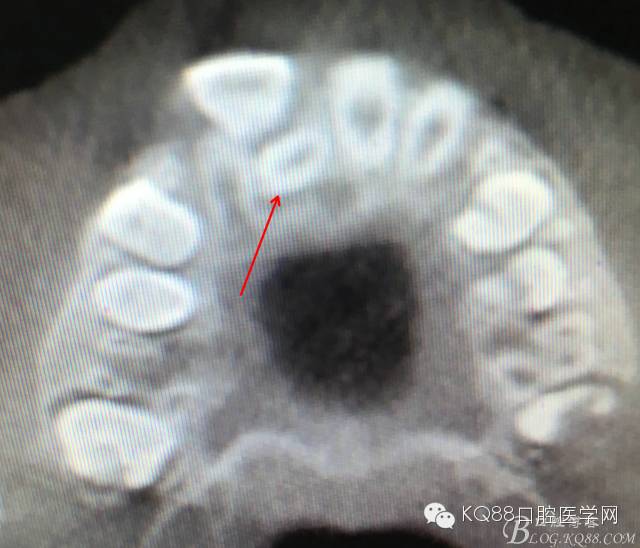

圖3.水平方向觀察多生牙與11和12之間的關(guān)系:多生牙牙冠緊鄰11與12牙根。